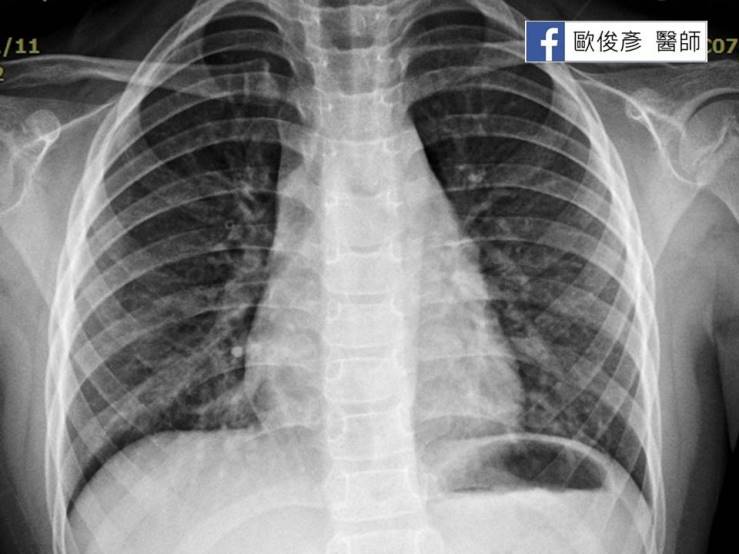

第二就是參考抽血的報告,如果白血球和發炎指數低,可以判斷兒童得到非典型肺炎。也可以從X光片看看有沒有出現浸潤或是大葉性肺炎來判斷。